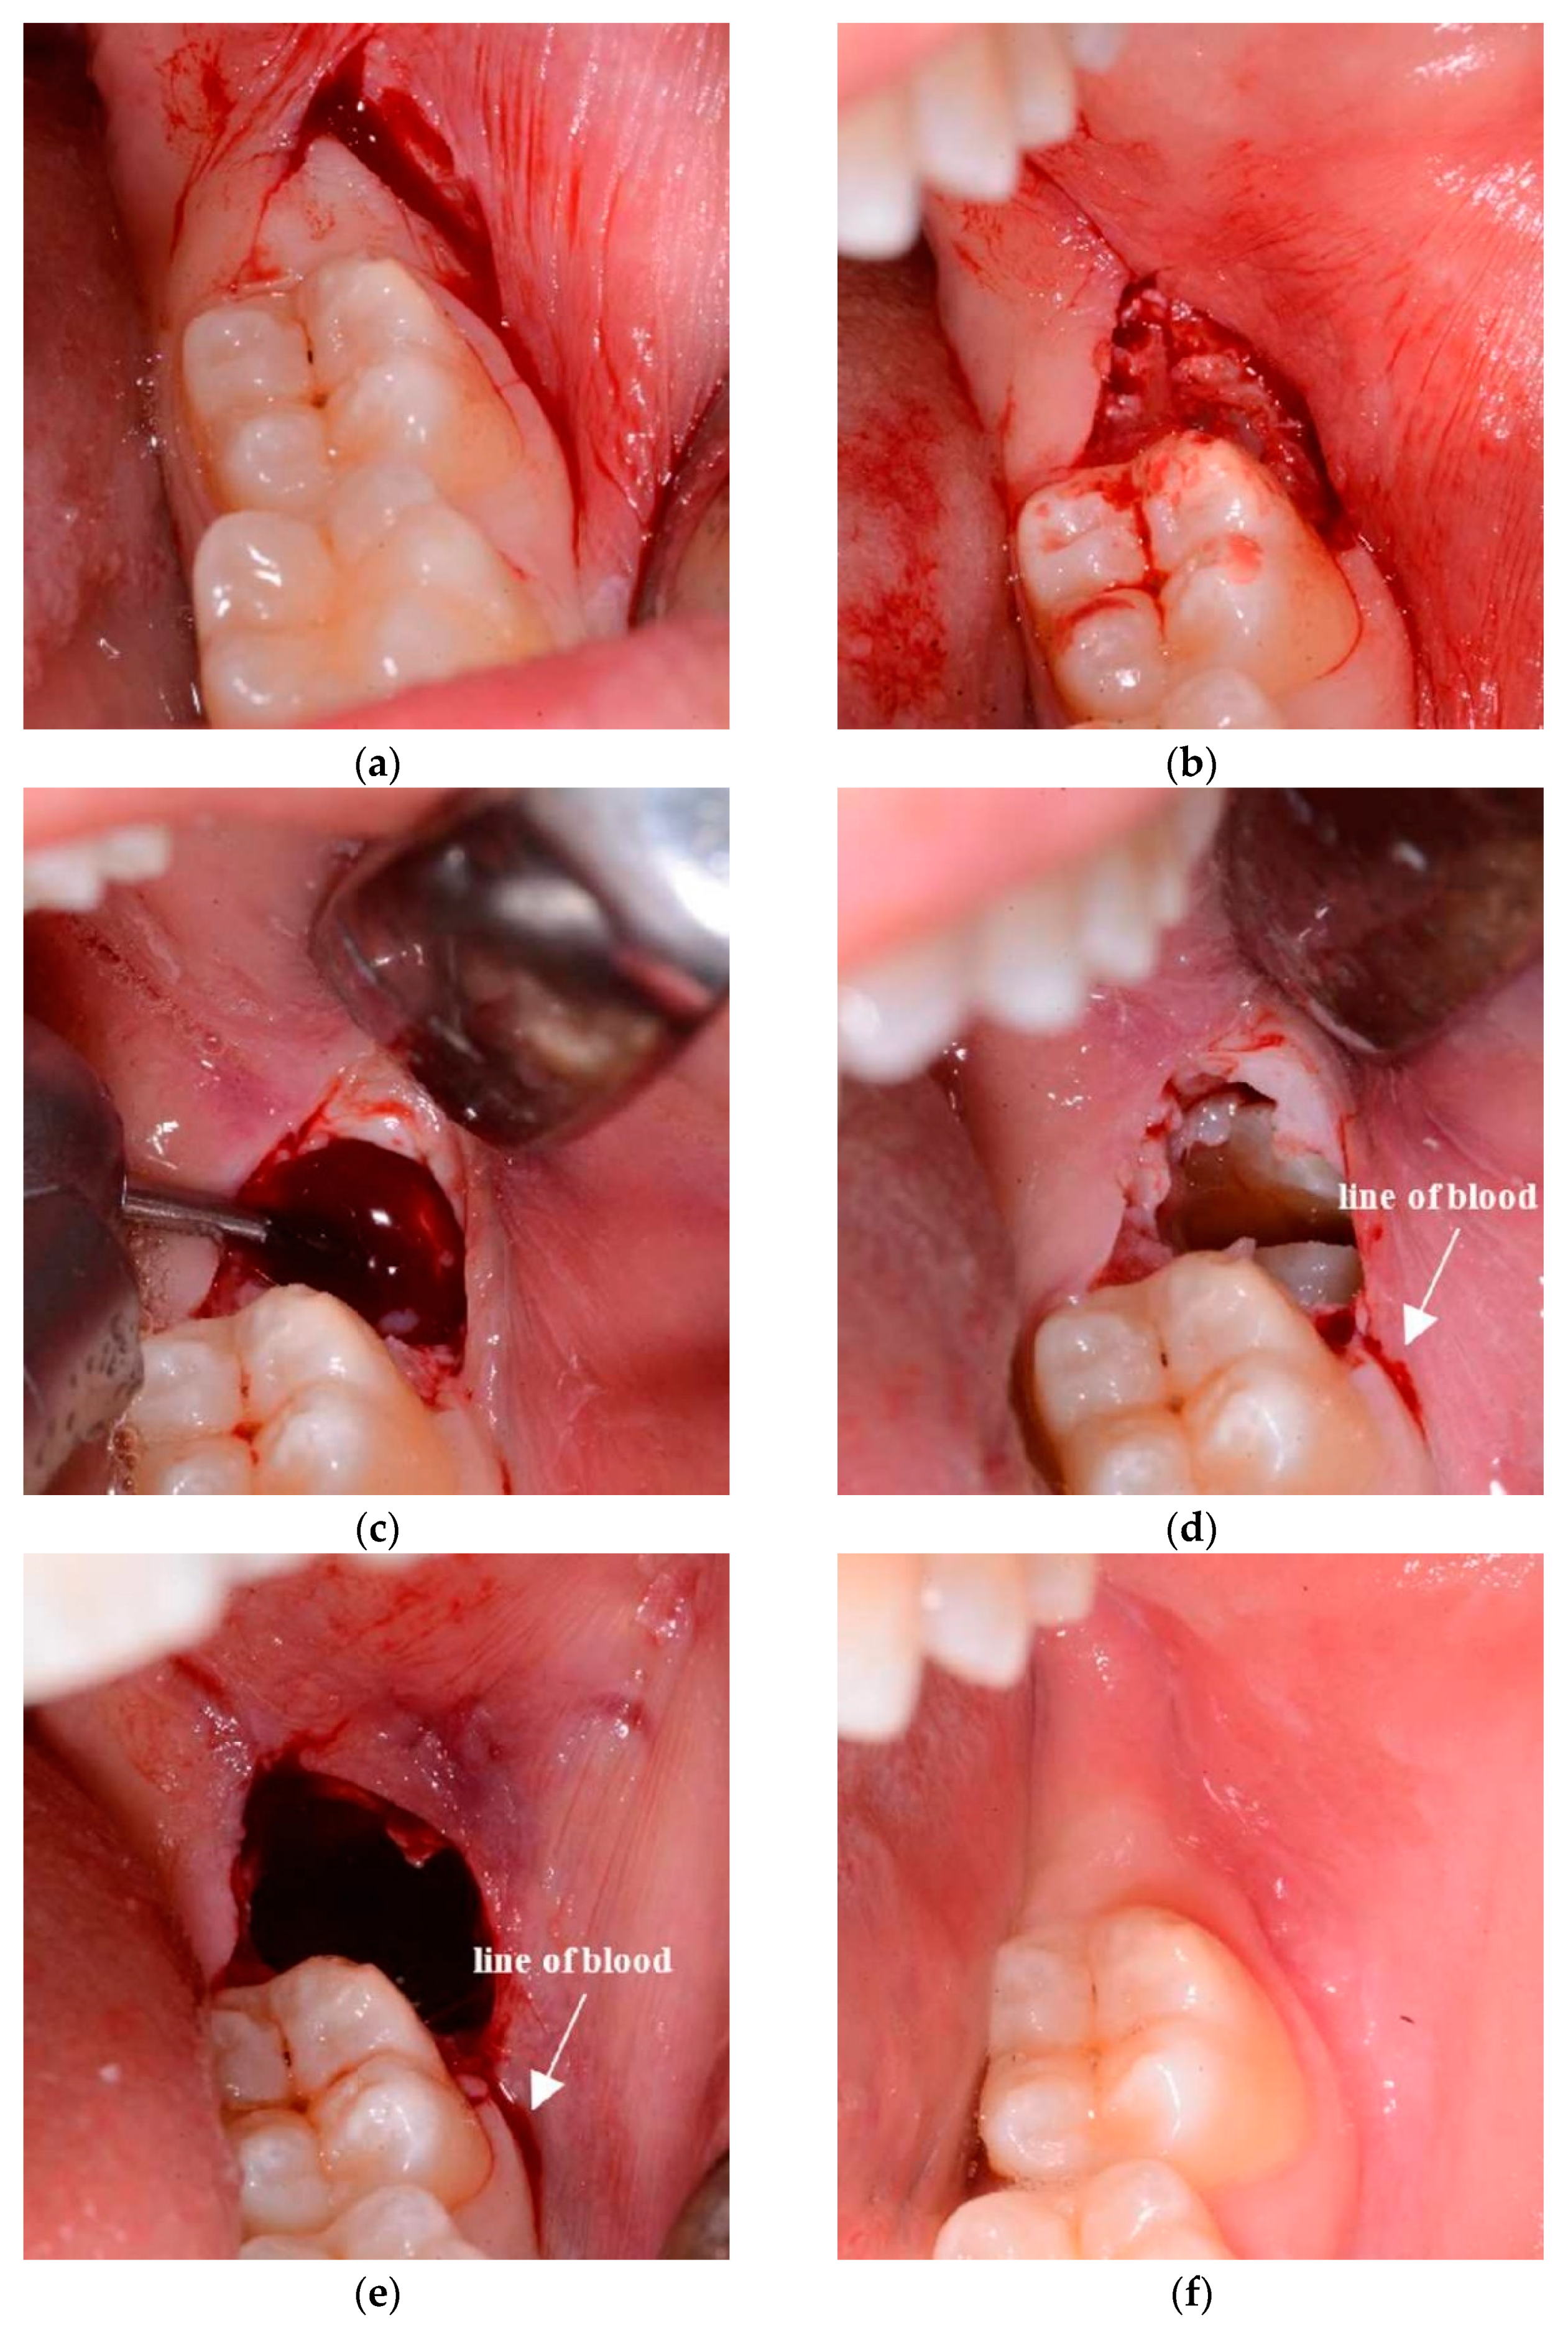

2.2. Surgical Design